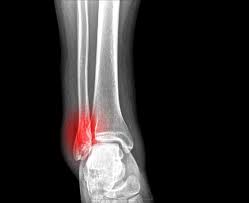

Gãy xương chày là gãy xương ở cẳng chân, là một trong hai xương lớn ở cẳng chân. Các triệu chứng của Gãy xương chày có thể dao động từ bầm tím đến đau dữ dội ở cẳng chân, tùy theo theo mức độ chấn thương. Để chẩn đoán loại chấn thương, bác sĩ sẽ làm khám lâm sàng và yêu cầu một số Xét nghiệm để xem hình ảnh gãy xương chày.

Xét nghiệm như X-quang và các chẩn đoán hình ảnh như chụp CT được khuyến khích. X-quang giúp xác nhận gãy xương và cũng tìm hiểu đầu gối hoặc khớp mắt cá chân có bị ảnh hưởng bởi gãy xương không.

Sau khi đọc hình chụp X-quang, nếu bác sĩ nghi ngờ đầu gối hoặc mắt cá chân bị ảnh hưởng, bạn sẽ cần chụp CT.